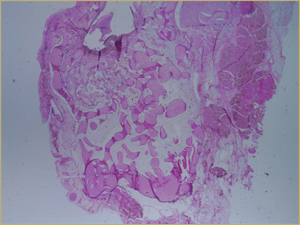

After 8 Weeks

By 8 weeks, all of the sinuses appeared histologically similar (Figs. 7–10). The mature lamellar bone that had been grafted in the autogenous bone group had been remodelled and was no longer present. Similarly, the numerous small-diameter woven bony trabeculae seen at 2 weeks in the BMP groups were no longer present. The sinuses all contained mature, small-diameter lamellar bony trabeculae. No qualitative histologic differences were apparent among the 5 treatment groups at 8 weeks (Figs. 7–10).

Figure 9: Low-power histologic examination of rabbit maxillary sinus augmented with bone morphogenetic protein at 8 weeks after procedure. H&E stain, 100× magnification.